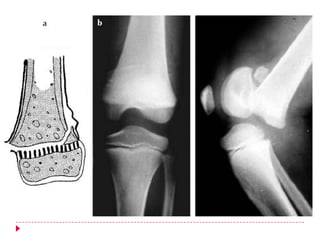

   Clasificación de Salter y Harris

   Tipo II (75%)  Decolamiento epifisiario + fractura

metafisiaria

   En una lesión de la placa epifisaria tipo que es el tipo más

común, el trazo de fractura se extiende a lo largo de la placa

epifisaria, para luego discurrir hacia la metáfisis, originando el

familiar fragmento metafisario triangular, a veces referido

como signo de Thurston Holland.

   Este tipo de lesión ocurre en niños por encima de los 10 años

y es el resultado de una lesión cizallante

   o por avulsión.

   El periostio es arrancado en el lado convexo de la

angulación, pero permanece integro en el lado cóncavo, es

decir, en el lado donde se encuentra el fragmento metafisario.

   La reducción es relativamente fácil de obtener y de

mantener, ya que el periostio intacto y el fragmento

metafisario actúan de bisagra, impidiendo la hipercorrección.

   Las células en crecimiento de la placa epifisaria permanecen

con la epífisis y, por tanto, el pronóstico es, casi

siempre, excelente con respecto al crecimiento y sin afectar el